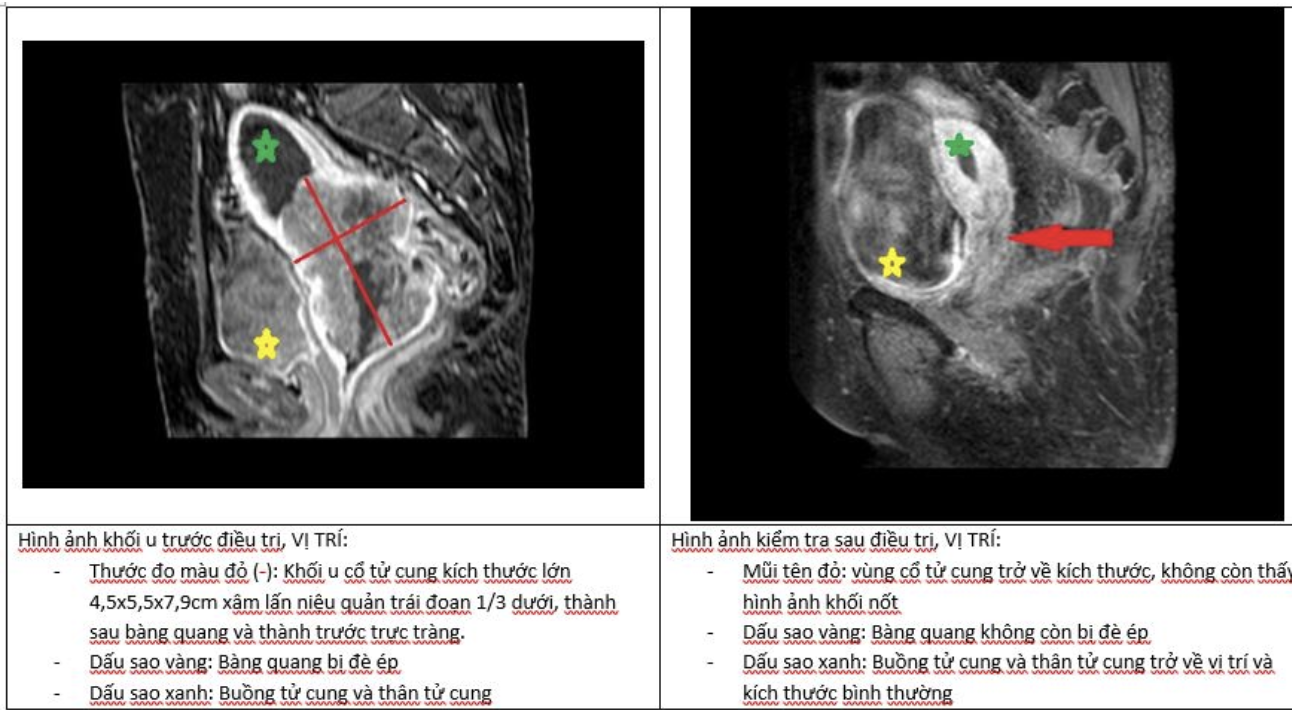

H́nh ảnh sau 4 tháng điều trị (ảnh BSCC).

Sau khi thăm khám, làm đầy đủ xét nghiệm và chẩn đoán h́nh ảnh, bác sĩ đă xây dựng một phác đồ điều trị đa mô thức: xạ trị chiếu ngoài kết hợp với hóa trị hàng tuần, sau đó tiếp tục xạ trị áp sát – một kỹ thuật hiện đại cho phép đưa liều xạ trực tiếp vào vùng tổn thương, giúp tăng hiệu quả điều trị và giảm ảnh hưởng lên các mô lành xung quanh.

Sau hơn 4 tháng bệnh nhân kiên tŕ điều trị theo phác đồ, kết quả tái khám cho thấy khối u không c̣n xuất hiện, các h́nh ảnh chẩn đoán đều b́nh thường.